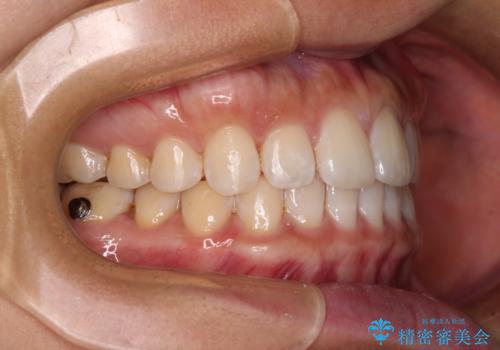

【モニター】前歯のすきっ歯をインビザラインで改善

- 上顎前歯の隙間と口元の突出感を気にして来院された患者様です。

高校生の時に行った矯正治療の後戻りであり、歯列不正は軽度であったので、インビザラインにて治療を行うこととしました。

すきっ歯はあっという間に後戻りを起こすので、可及的に後戻りを防止するために、上下前歯部を舌側からワイヤーで固定しています。

通常は下顎前歯のみに行っていますが、空隙歯列弓では上顎でも行っています。